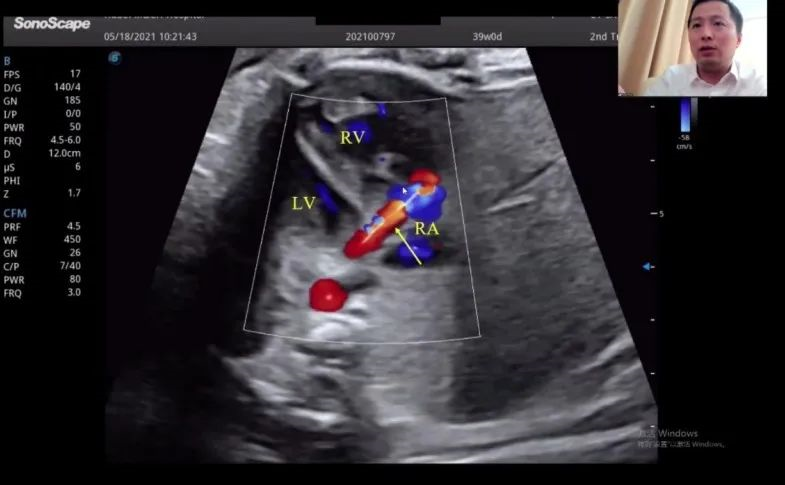

浙江大學(xué)醫(yī)學(xué)院附屬邵逸夫醫(yī)院的趙博文教授聚焦先天性心臟疾?。–HD)的產(chǎn)前診斷,通過特殊病例的展示講解,包括法洛四聯(lián)癥(TOF,一種常見的先天性心臟畸形)的時空關(guān)聯(lián)成像技術(shù)(Spatio-Temporal Image Correlation,STIC)、大動脈完全轉(zhuǎn)位(cTGA)和右心室雙出口(DORV)的圖像,前瞻性地提出智能胎心的應(yīng)用場景。“胎心檢查人工智能的應(yīng)用非常有價值,能夠縮短檢查時間,提高臨床的診療效率,”趙教授如是說。

湖北省婦幼保健院的趙勝教授在會上帶來了胎兒冠狀動脈瘺超聲診斷研究的分享。趙教授表示,冠狀動脈瘺在妊娠晚期可通過超聲檢查顯示出來,經(jīng)線圈栓塞或冠狀動脈瘺術(shù)后,進(jìn)一步的臨床過程通常較為順利。